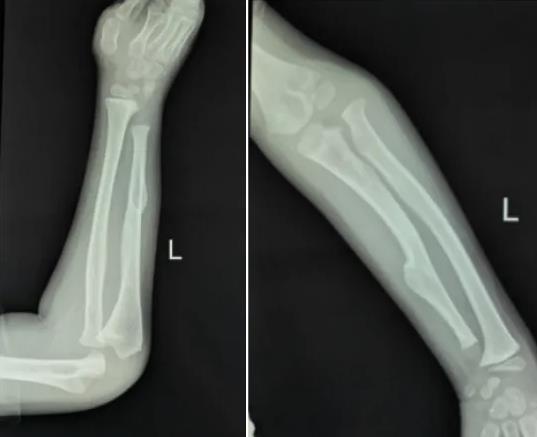

前臂畸形

软骨瘤形成,尺骨短缩,桡骨头脱位

手术成功完成,外固定满意

术后X线:尺骨已截骨,外固定牢固